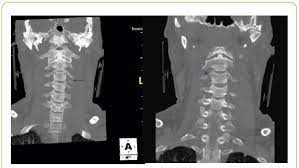

The transverse foramen is an opening on each of the transverse processes of the cervical spine which gives passage to the vertebral artery and vein and a sympathetic nerve plexus. There are two transverse processes that extend off each vertebra in the details: Transverse process fractures are common sequelae of trauma, although they are considered a minor and stable lumbar spine fracture. Transverse processes are typically fractured in direct blows from athletics touch or impact from falls from bikes/motorbikes or by heights. However, postmortem computed tomography (pmct) has made detection of this type of injury easy. There are two transverse processes that extend off each vertebra in the spine, one on each side. A transverse process fracture is a break in 1 or more transverse process. In 78% of transverse process fractures, ct scanning showed that the fracture extended into the transverse foramen. A transverse process fracture is considered as a rare injury. A transverse process fracture is a break in 1 or more transverse process. What is a transverse process fracture? Transverse process fractures caused by stress are likely under detected since even an acute transverse process fracture requires a high index of suspicion to be correctly identified(4,7). If ct confirms isolated injury lateral flexion/extension views are indicated to rule out dynamic instability.

However, postmortem computed tomography (pmct) has made detection of this type of injury easy. There are two transverse processes that extend off each vertebra in the details: What is a transverse process fracture? It may occur as an avulsion fracture due to strong contracture of the muscles. It occurs as a result of sudden and extreme trauma. If ct confirms isolated injury lateral flexion/extension views are indicated to rule out dynamic instability. Vertebral angiography, performed in eight patients with fractures involving the transverse foramen, showed dissection or occlusion of the vertebral artery in seven (88%) instances. This part extends out from the side of the main body of the bone (called the vertebral body). A transverse process fracture at the level of l5 is a surrogate marker of vertical instability of the pelvic fracture due to the attachment of the iliolumbar ligaments. We retrospectively reviewed the reports of lumbar spine and abdominopelvic ct scans from 2017 and 2018 to classify the types of spine fractures, their mechanism of injury, treatment and. Up to 60% of lumbar transverse process fractures identified on ct will be missed on plain radiographs. In 78% of transverse process fractures, ct scanning showed that the fracture extended into the transverse foramen. Transverse process fractures identified on helical computed tomography (ct) scans without the presence of any other fracture or.